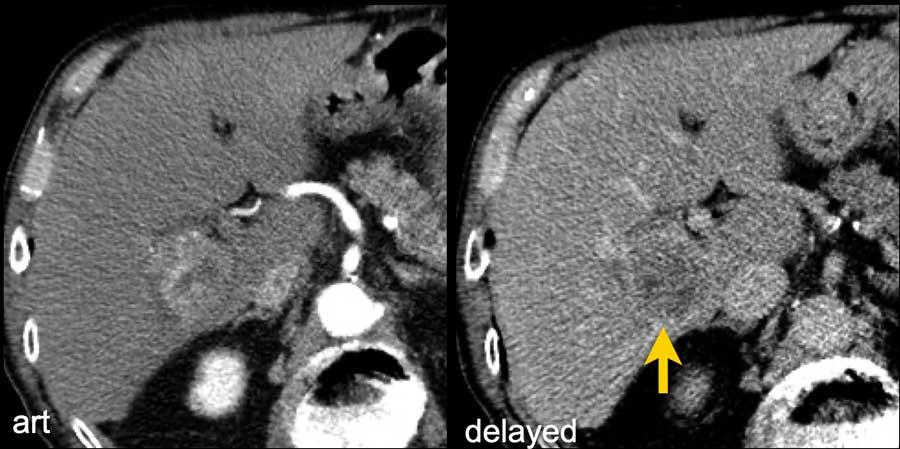

Các hình ảnh cho thấy một tổn thương ngấm thuốc động mạch dạng viền nhẹ ở phân thùy V có thải thuốc.

Có thể thấy một vùng giảm ngấm thuốc dạng tuyến tính kéo dài từ khối u, gợi ý khối u trong tĩnh mạch (mũi tên vàng).

Vì chúng ta không hoàn toàn chắc chắn đây là huyết khối do khối u, nên không thể phân loại trường hợp này là LR-TIV.

Một CT theo dõi được thực hiện, cho thấy tiến triển nặng của khối u cũng như xâm lấn mạch máu vào nhánh tĩnh mạch cửa phải trước (mũi tên trắng).

Lúc này chúng ta có thể xác định chắc chắn sự xâm lấn khối u vào tĩnh mạch cửa.